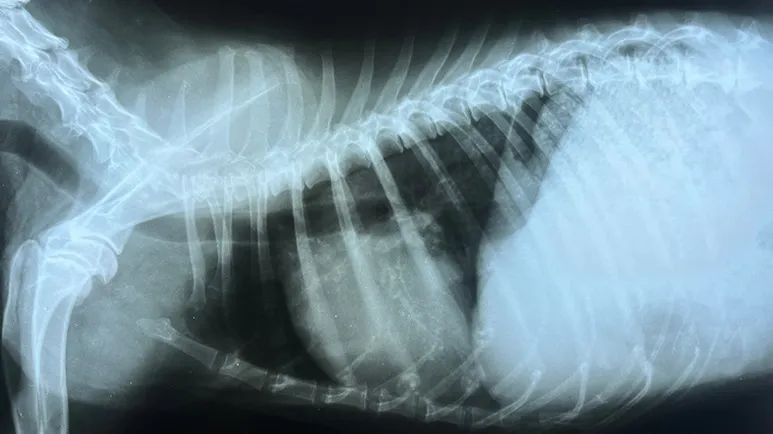

- Blood tests, chest radiographs (X-rays), electrocardiograms, and echocardiograms (ultrasound of the heart) help pinpoint the cause so your veterinarian can decide whether to monitor, start medications, recommend procedures, or adjust lifestyle and nutrition for support

Some dogs also need chest radiographs (X-rays) or an electrocardiogram (ECG), especially if the rhythm sounds abnormal. Bloodwork may be added if the murmur could be due to anemia, infection, hormone imbalances, or other systemic conditions.15